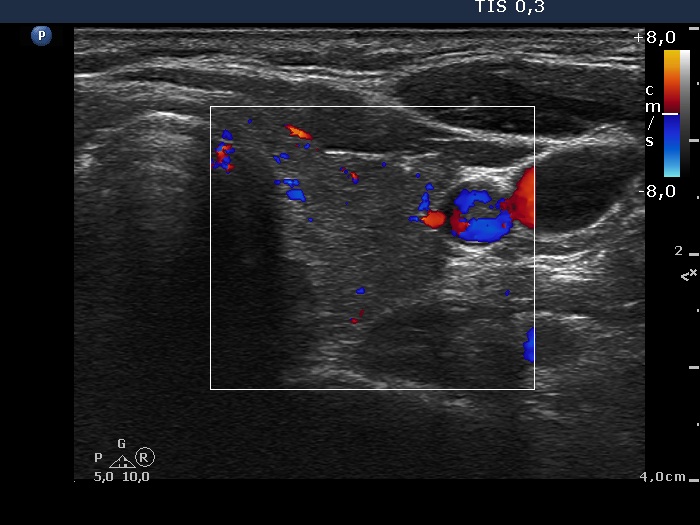

Ultrasonography: The thyroid was minimally-moderately hypoechogenic and presented fibrosis. There was a cystic lesion in the lower dorsal part of the right thyroid bed.